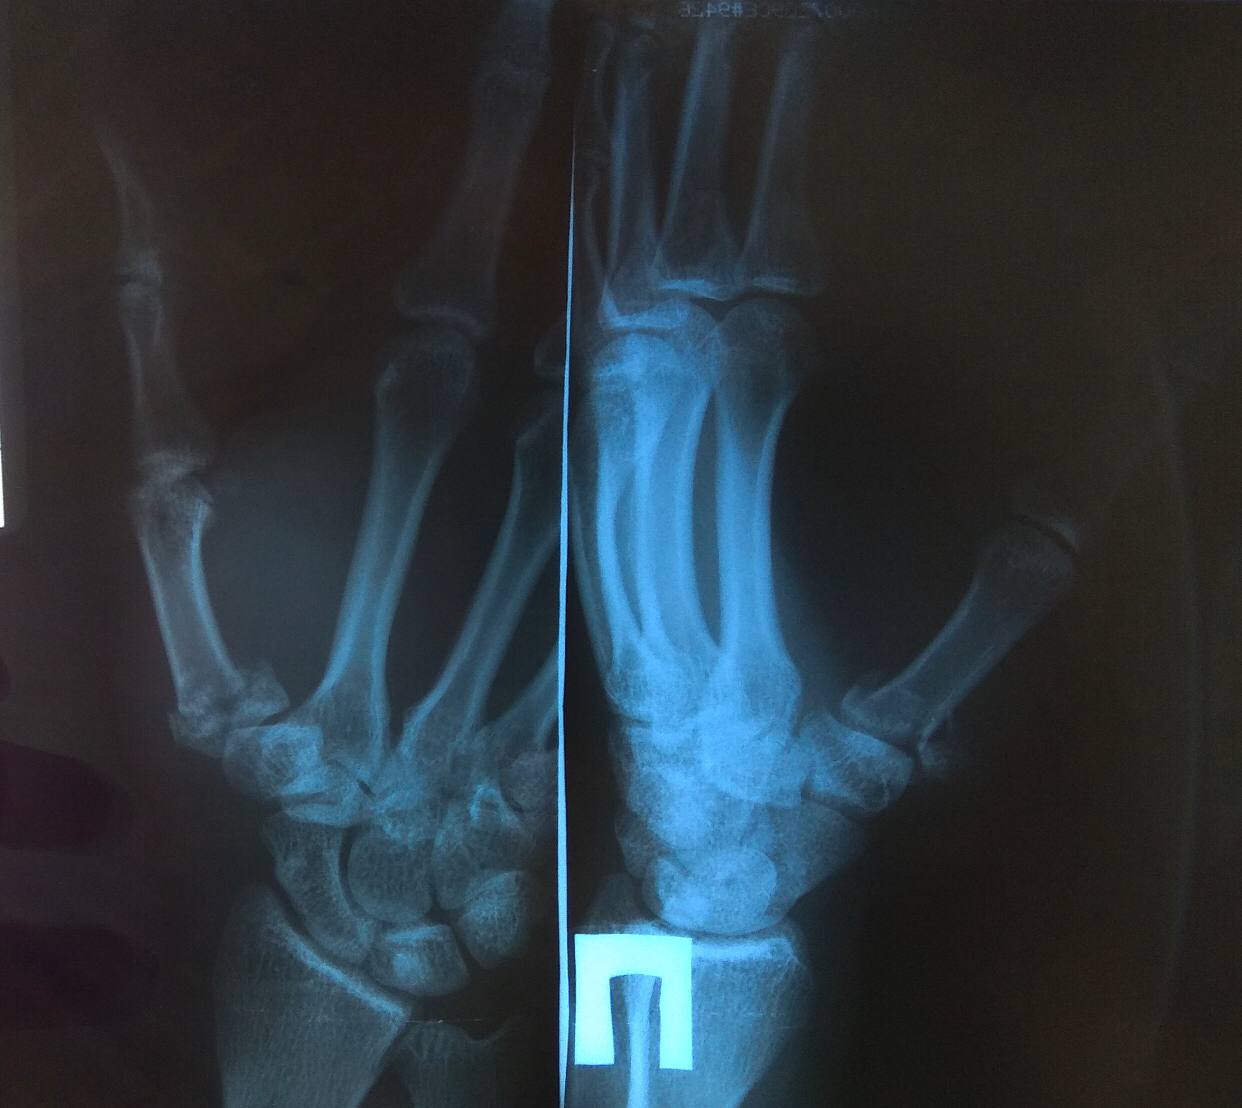

Уважаемые коллеги, подскажите пожалуйста есть что серьёзное или нет?

Спортивная травма, играл в волейбол, в большой палец прилетел мяч

Перелом Беннета